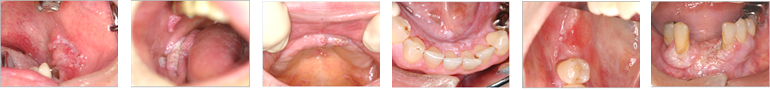

●口腔がんの症例写真

舌がん

舌がん(舌にできるがん)は口腔がんの中でも最も多いがんです。そのほとんどで、舌縁部(舌の側面)や舌の裏側にでき、舌の上面にできることはほとんどありません。

粘膜面が、赤くなったり、白くなったり、表面が凸凹したり、潰瘍ができたりします。 触ってみて、何か粘膜の下に「かたまり」や厚みのある部分を触れたら要注意です。

開業医だから発見できる口腔がん そのサインの見つけ方と対処法より引用

歯肉がん

歯の生えている部分の粘膜を歯肉と言います。この部分の粘膜が赤くなったり、白くなったり、表面が凸凹したり、潰瘍ができたりします。

歯周病でもないのに、「歯がぐらぐらしてきた」や「腫れてきた」、「歯を抜いた後がなかなか治らない」などの症状のこともあります。歯ぐきの表側ではなく裏側にできることも多いので要注意です。

頬粘膜がん

いわゆる頬の内側、口の中の粘膜に出来るがんです。噛んだり、傷つけた覚えがないのに、粘膜面が、赤くなったり、白くなったり、表面が凸凹したり、潰瘍ができたりします。触ってみて、何か粘膜の下に「かたまり」や厚みのある部分を触れたら要注意です。親知らずの生える部分の粘膜部分も後発部位の一つです。